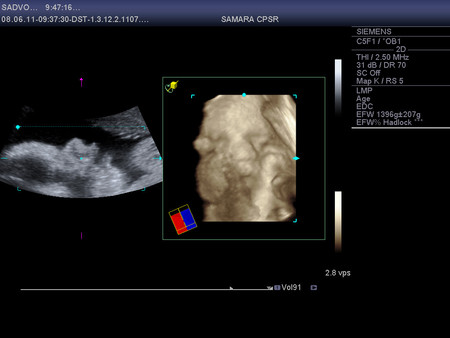

. Он все понимает. Вчера заявил, что обязательно будет присутствовать на родах как и в прошлый раз, т.к. по-другому просто не может и ему будет легче со мной, чем где-то тупо ждать. Мне безусловно приятно. Его присутствие, поддержка, помощь для меня не оценимы. Такая непередаваемая между нами близость была в тот момент и сейчас, когда вспоминаем день рождения нашего ребенка. Ивану тоже достается от меня по полной программе, мне его даже жалко, но я ничего не могу с собой поделать. Порой у меня ощущение,что он просто издевается надо мной. Стал капризным, требовательным, нервным, истерит по любому поводу,если не удовлетворить его просьбу. Толи из-за зубов,которые продолжают резаться,толи из-за огромного прорыва в речи. Стал говорить много слов, повторяет почти все,что произносят взрослые. От мультиков вообще не оторвать. Любимые про котенка "Гав", Карлсона и паровозик из Ромашково. Готов смотреть целыми днями из-за чего у нас с ним бесконечная борьба происходит. В общем последняя неделя в эмоциональном плане была не из легких. На приемы в ЖК езжу теперь каждую неделю, анализы и КТГ хорошие, гемоглобин даже повысился каким-то чудесным образом до 103. Вес 56 кг. Сходила на УЗИ. Лежит головой вниз, обвития нет, кровотоки хорошие, все органы в порядке, вес примерно 1720. Врач сказала,что ребенок небольшой, к родам будет примерно 3100 (Ваня родился 3435). Плацента поднялась до 6 см, как раз то, что нужно. Посмотрела в 4D кажется совсем не похож на Ваню, а Тимка говорит, что копия (наверное очень хочет, чтоб и второй был похож только на него

). А еще он волосатый (первый раз на УЗИ видела волосы), прям длинные волосы торчат на голове.